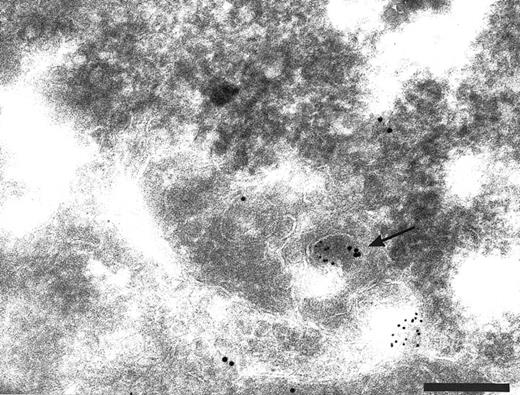

Cryosections of HUVEC showing adsorption control results. The sections were incubated with anti-TFPI diluted in medium containing rTFPI, and then with protein A-gold. (A) There is no label over the region of the Golgi complex (G) even though some nonspecific label (arrowheads) is seen over the nucleus. Bar = 0.5 μm. (B) Although the adsorption control did not completely abolish labeling (arrowheads), the amount of label is reduced and no label is observed over the many intracellular vacuoles (v) characteristic of these cells. Bar = 0.5 μm.

Intracellular localization of TFPI. The normal distribution of TFPI within endothelial cells, maintained in vitro, was examined on thin cryosections labeled with specific antibodies and colloidal gold probes. Label was seen associated with the cell surface and with many intracellular structures including the Golgi complex (Fig 1) and many organelles with vesicular profiles (data not shown). The surface label was irregular with noticable variation of signal intensity between cells and different parts of the same cell (data not shown). The signal appeared to concentrate over the thin cellular processes of the outer perimeter of these flat endothelial cells (Fig 1). The frequency of anti-TFPI labeling was 3.5 ± 0.5 gold particles per 10-μm length of plasma membrane (data not shown). If the anti-TFPI IgG was preadsorbed with recombinant TFPI before labeling, the frequency of TFPI labeling was 0.7 ± 0.3 gold particles per 10-μm length of plasma membrane (data not shown) and also resulted in an almost total abolition of signal over the Golgi complex (Fig 2A) and cytoplasmic vesicles (Fig 2B). Similar labeling patterns on sections through intact veins of umbilical cords were observed using αTFPI and rTFPI plus αTFPI, respectively (data not shown).